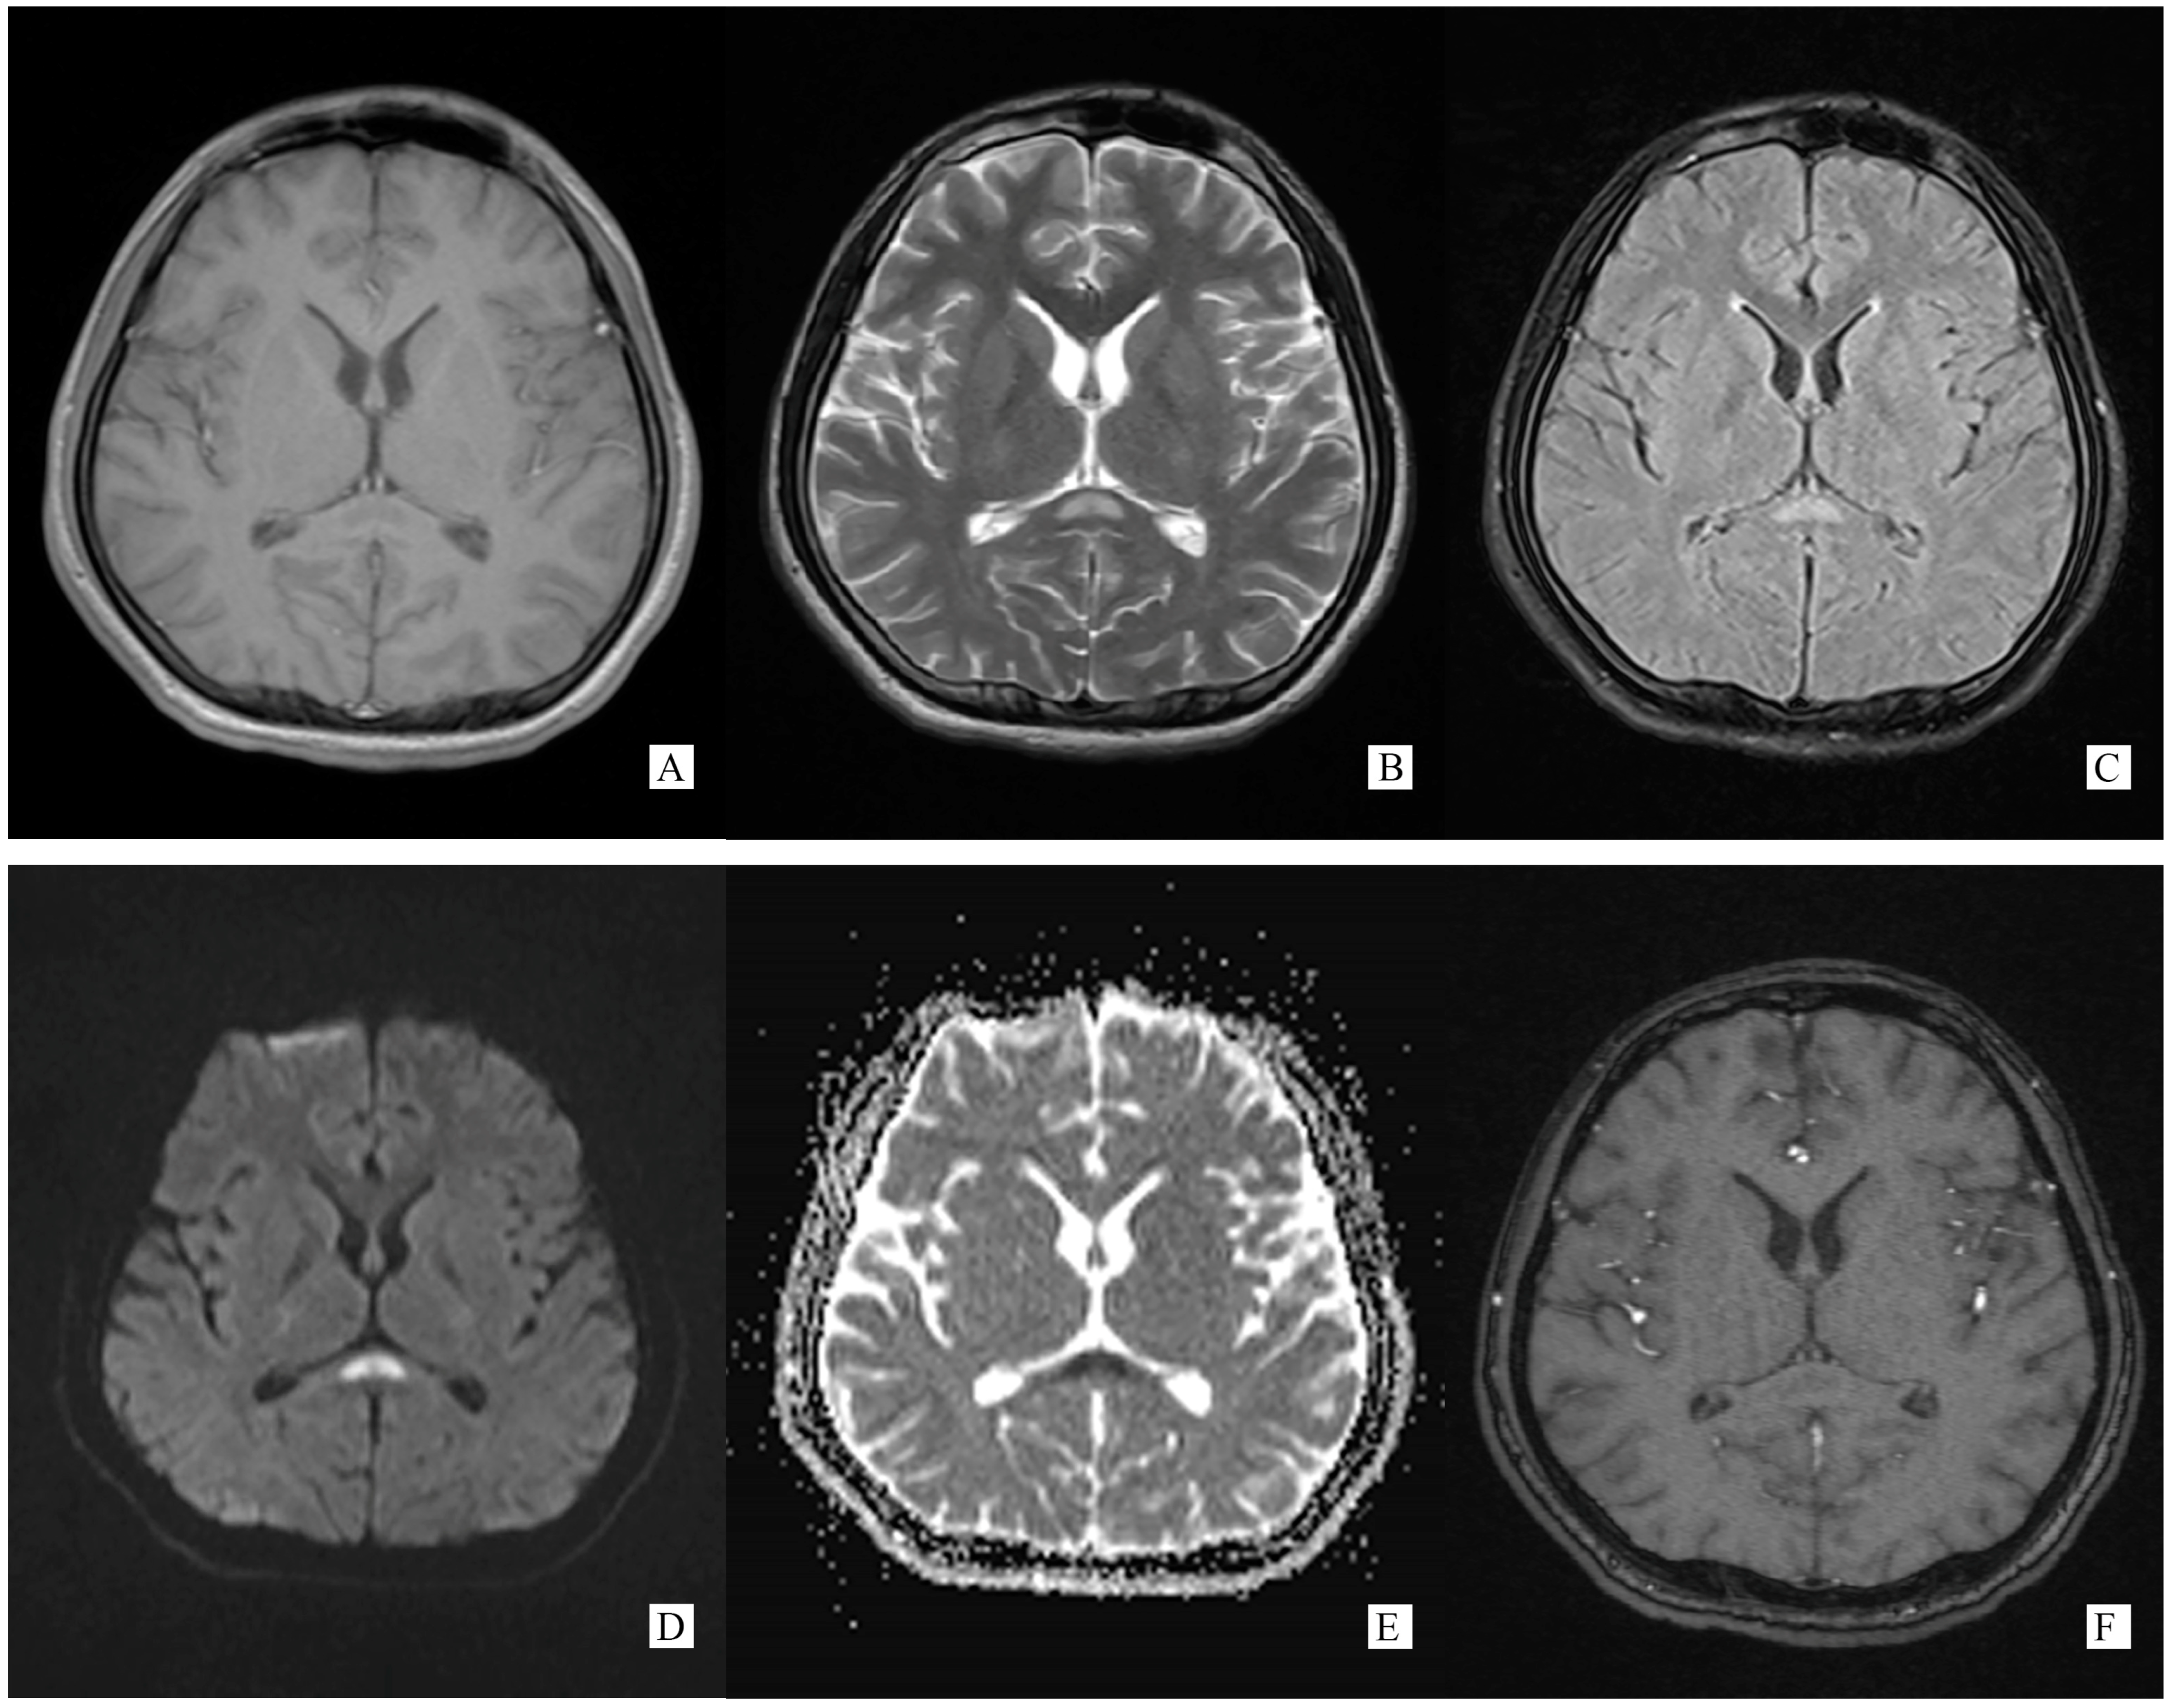

Figure 1.

(Performed on 5 November 2021). (A) Axial T1 weight brain MRI image showing an oval hypointense lesion on SCC. (B) Axial T2 weight brain MRI image showing an oval hyperintense lesion on SCC. (C) Axial T2 flair weight brain MRI image showing an oval hyperintense lesion on SCC. (D) Axial DWI weight (b = 1000) brain MRI image showing an oval hyperintense lesion on SCC. (E) Axial ADC weight brain MRI image showing an oval hyperintense lesion on SCC. (F) Axial post-gadolinium T1-weighted brain MRI showing no enhancement on SCC lesion.

A total of 6 days after onset, on 3 November 2021, he turned to a higher-level hospital for further evaluation and treatment. Lumbar puncture showed CSF ICP 350 mmH2O, glucose 2.25 mmol/L, chlorine 118.2 mmol/L, and protein 1.27 g/L. WBC counts were normal. Cerebral MRI demonstrated an abnormal signal on SCC (Figure 1). Based on these results, he was considered as meningoencephalomyelitis, and was given ceftriaxone to anti-infective. However, there was no improvement in the condition.

Generally, typical features of autoimmune GFAP astrocytopathy present as a linear, radial perivascular enhancement pattern on brain MRI, and central longitudinally extensive enhancement pattern on spinal cord MRI [7]. RESLES is typically classified into two patterns on MRI: type I is an isolated lesion on SCC, type II is a lesion in SCC expending to callosal fibers, cerebral white matters or anterior portion of corpus callosum. No matter type I or type II, lesions can be significantly shrunk or totally disappeared within a month, accompanied with the relief of symptoms [8]. In the MRI of our case, the lesion was located in the SCC, manifested a hypointense signal on T1WI and hyperintense on T2WI and DWI, reversibly, which is similar to type I RESLES, but unlike the typical autoimmune GFAP astrocytopathy.